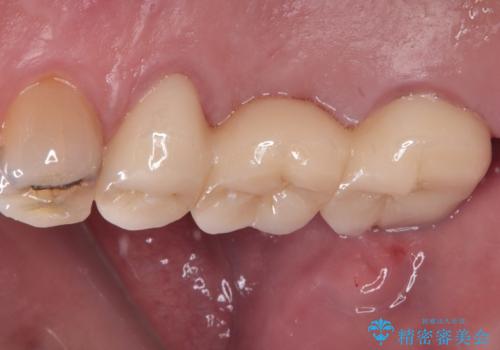

ブリッジ除去後痛みが引いたことを確認し、オールセラミックブリッジによる補綴治療を行うこととしました。

銀歯に隠れていて術前のレントゲンでははっきりと分かりませんでしたが、元々非常に大きなむし歯があったようで、銀歯の中で神経組織が壊死を起こしていました。

速やかに根管治療を行い、無事に痛みを取り除くことができました。